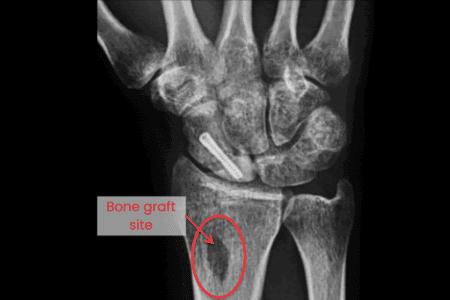

If a large gap is left in the bone due to severe fractures, a bone graft may be required to encourage healing. This involves: